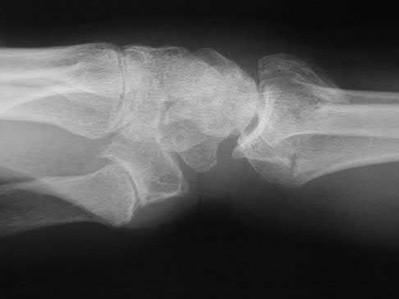

A 25-year-old woman sustains a fall on an outstretched hand. She complains of elbow pain. Examination reveals tenderness over the lateral elbow and pain on elbow motion. Injury radiographs and CT scans are shown in Figures A and B, respectively. What is the next best step?

This patient has Mason II radial head fracture. ORIF will give the best results.

Non-/minimally displaced radial head fractures without a block to rotation can be managed nonoperatively. Complete articular fractures with >=3 fragments do better with radial head replacement. Indications for ORIF include large articular surface fragments, > 2 mm of displacement, mechanical block to forearm rotation, or associated fractures or ligament injuries requiring surgery.

Pike et al. retrospectively compared patients undergoing ORIF for isolated radial head fractures with radial fractures associated with other fractures/dislocations. They found no differences in pain/disability and complications or secondary capsular release between groups.

Yoon et al. retrospectively compared isolated partial articular displaced (2-5mm) radial head fractures treated nonoperatively vs ORIF. They found no clinical benefit with ORIF compared to non-operative management. The ORIF

group had more complications. Younger patient age and larger fracture displacement favored operative intervention. Younger patients fared worse.

Figures A and B are radiographs and 3D reformatted CT images showing a displaced partial articular radial head fracture.